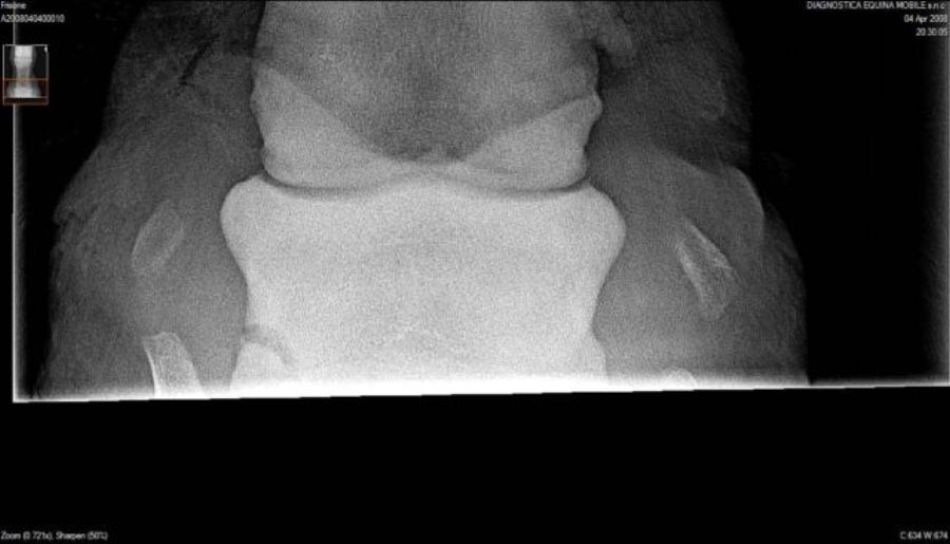

Briefly the radiographs show wear and tear changes common in many older working horses: osteophytes (bone spurs), calcification on the anterior of the pastern, partial calcification of the collateral cartilages. I do not see any definitive congenital defects. The talus of the hock has some odd irregularity but I don't review many digital radiographs and this could be a range of normal for it.

It depends on what you mean by arthritis. Do I see any lesions that correlate with painful arthritis 100% of the time? The answer is no. But yes there are osteophytes visible in both the tibiotarsal and proximal intertarsal joints (the upper two). The talus within the tibiotarsal joint also show evidence of bony resorption and production. These are markers for the presences of osteoarthritis.